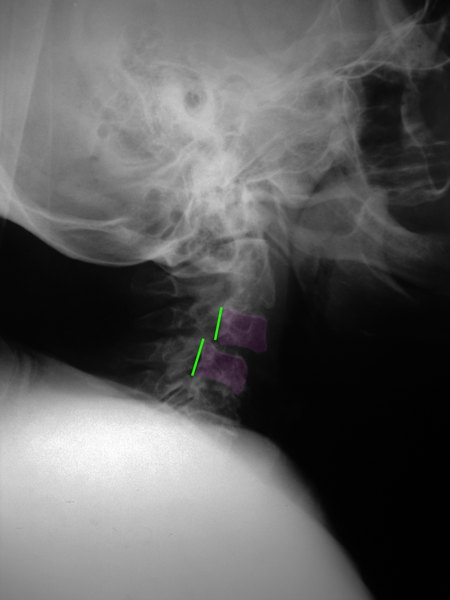

Η συγγενής μορφή της οσφυϊκής σπονδυλολίσθησης λέγεται δυσπλαστική και ανευρίσκεται συνήθως σε συνδυασμό με δυσχιδή ράχη, ένα έλλειμμα της σύγκλισης του σπονδυλικού σωλήνα ο οποίος παραμένει ανοιχτός στην οπίσθια περιοχή του. Η ισθμική σπονδυλολίσθηση ή σπονδυλόλυση ανευρίσκεται σε ένα ποσοστό περίπου 5 % των οσφυϊκών ακτινογραφιών (συνήθως στο επίπεδο Ο5-Ι1) και οφείλεται σε μικρό τραυματισμό ή κάταγμα μέρους του σπονδύλου. Η εκφυλιστική σπονδυλολίσθηση είναι η συχνότερη, απαντάται σε 7-8% των οσφυϊκών ακτινογραφιών. Εκφυλιστική σπονδυλολίσθηση μπορεί να παρατηρηθεί και στην αυχενική μοίρα της σπονδυλικής στήλης. Τέλος τραυματικές και παθολογικές σπονδυλολισθήσεις παρατηρούνται σε όλη την έκταση της σπονδυλικής στήλης και είναι απότοκοι σοβαρών τραυματισμών ή άλλης παθολογίας (όπως όγκοι και λοιμώξεις) αντίστοιχα.

Το συνηθέστερο σύμπτωμα της σημαντικής οσφυϊκής σπονδυλολίσθησης είναι ο πόνος, τοπικός αλλά και αντανακλούμενος σε ένα ή και τα δύο κάτω άκρα όταν πιέζονται τα οσφυϊκά νεύρα. Στην ισθμική σπονδυλολίσθηση σπάνια υπάρχει στένωση του οσφυϊκού σπονδυλικού σωλήνα (μόνο πίεση των οσφυϊκών νεύρων στα τρήματα εξόδου από την σπονδυλική στήλη) κάτι το οποίο συμβαίνει κατά κανόνα στην εκφυλιστικής αιτιολογίας σπονδυλολίσθηση και προκαλεί νευρογενή διαλείπουσα χωλότητα (αδυναμία στα πόδια μετά από βραχεία βάδιση). Στην αυχενική μοίρα της σπονδυλικής στήλης μπορεί να επέλθει πίεση επί του νωτιαίου μυελού με αποτέλεσμα αυχενική μυελοπάθεια ή/και στένωσεις των νευρικών τρημάτων με αυχενοβραχιόνιο σύνδρομο σε ένα ή και στα 2 άνω άκρα. Πρέπει εδώ να σημειωθεί ότι η ύπαρξη σπονδυλολίσθησης στον απεικονιστικό έλεγχο, στην περίπτωση της εκφυλιστικής και ισθμικής σπονδυλολίσθησης, δεν συνεπάγεται αυτόματα ύπαρξη συμπτωμάτων, πολλές, ιδιαίτερα αυτές με μικρό βαθμό βαρύτητας, είναι ασυμπτωματικές όταν ανακαλύπτονται.